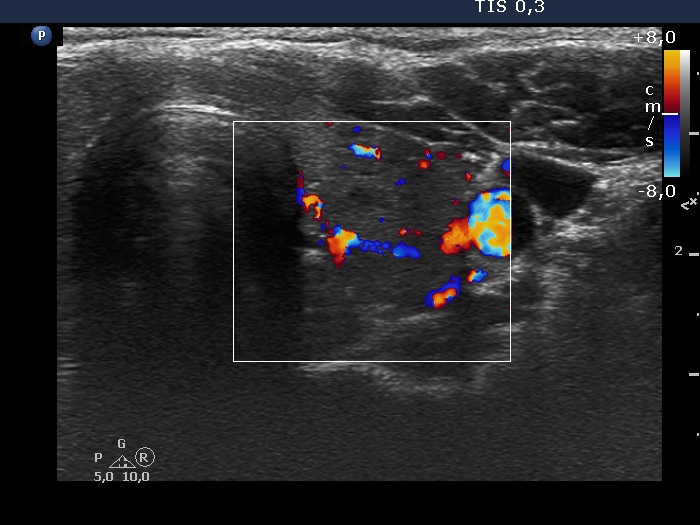

Lymphocytic thyroiditis - case 1580

Eleven months after the second delivery (ultrasonographic picture 6)

Left lobe, transverse scan, color Doppler mode. The vascularity has increased since the last visit.